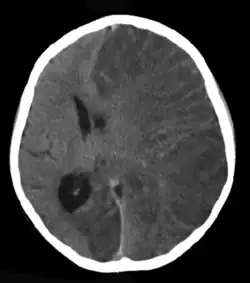

![]() Obraz w tomografii komputerowej głowy ośmioletniej dziewczynki z zapaleniem mózgu Rasmussena. | |

Badania neuroobrazowe wykazują postępujący zanik płata skroniowego[9]. W MR na wczesnym etapie choroby w obrazach T2 i FLAIR stwierdza się ogniska o podwyższonym sygnale w obrębie kory mózgu po stronie uszkodzonej. W późniejszych fazach choroby występują cechy połowiczego zaniku mózgu[5].